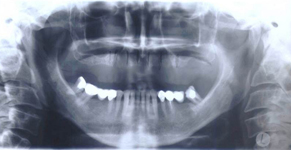

Augmentační postupy jsou zákroky minimálně invazivní až po náročnější operace upravující nedostatečnou nabídku alveolární kosti co do kvantity a kvality.

Tyto postupy nám umožní doplnit chybějící množství kosti v čelistech pacienta i zlepšit kvalitu kosti. Většinou se setkáváme s omezenou nabídkou kostní tkáně díky resorpčním (úbytkovým) procesům způsobených věkem či vytržením zubu, přítomností anatomických struktur jako je čelistní dutina, nervový kanál nebo patologických či poúrazových stavů - cysty, zlomeniny.

V těchto případech musíme použít některou z následujících pomocných metod: